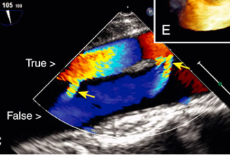

Type A aortic dissection

What is seen in the TEE image?

Incomplete separation in aortic dissection

What are the arrows pointing towards?